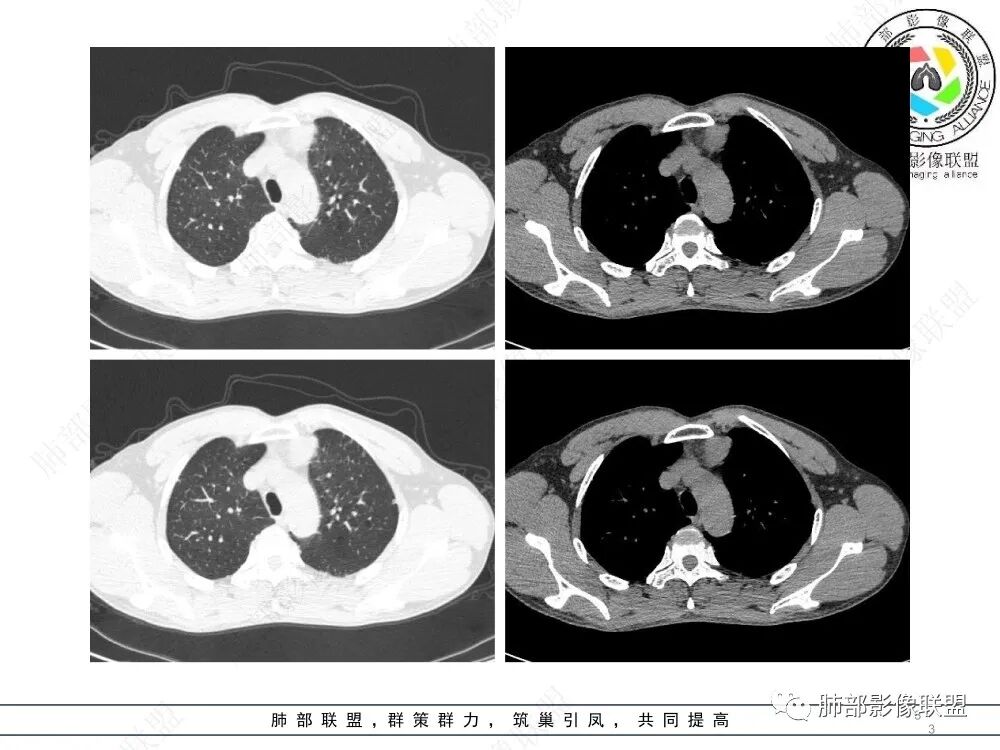

放射小白:男性47岁,前纵隔团块状占位,边界尚清,增强中度强化,内部疑似纤维分隔,常规考虑胸腺瘤可能(A/AB型),鉴别类癌、CD。

Yishion:晨读:纵隔占位,偏侧生长,边界清楚,有浅分叶,强化明显,其内似见纤维分隔,常规考虑胸腺瘤(AB型)。

宇宙:前纵膈偏左类圆形肿块,边界清晰光整,与大血管脂肪间隙清,密度均匀,轻中度强化,考虑胸腺瘤,A型?鉴别胸腺癌。

流心明智:男,47,咳嗽、咳痰1年余。胸部CT:前纵膈偏左类圆形肿块,瘤肺界面清晰光整,纵隔侧部分层面絮状影?平扫密度较均匀,增强后轻度强化,内可见宽带及线样低密度分隔。邻近左上肺受压凹陷。考虑胸腺肿瘤,AB型?胸腺Ca?鉴别淋巴瘤、N源性肿瘤、CD等。

南边:支持前纵隔、胸腺瘤首选,晨读其实定位上还是有点难度,定性常规还是考虑胸腺瘤,其他的几率比较低一些,需要鉴别的是胸膜SFT,神经源性,可惜的是没重建,一直在犹豫胸膜来源的可能性。

2、影像特点:前纵隔偏左侧软组织影,密度相对均匀,未见明显包膜钙化及实质内钙化,局部边缘浅分叶,周围脂肪间隙密度增高、浑浊,未见侵犯大血管、未见纵隔内淋巴结转移、未见侵犯心包内结构、未见胸膜转移结节、未见肿块沿着纵隔胸膜蔓延,未见胸腔积液。增强后动脉期不均匀强化,未见明显纤维分隔。

3、 病 例 小 结:40岁以上,前纵隔偏侧性生长的肿块,常规考虑胸腺瘤。难点就在于胸腺瘤的分型。但是对于前纵隔占位影像诊断的关键在于区分胸腺囊肿、胸腺瘤、胸腺癌及其他恶性肿瘤。至于胸腺瘤,主要在于判断有无侵袭性。